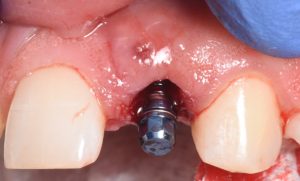

This video demonstrates immediate implant placement in the esthetic zone following atraumatic extraction of a lateral incisor. Emphasis is placed on preserving the hard and soft tissue architecture critical for predictable esthetic outcomes.

The procedure is presented step by step, including minimally traumatic extraction techniques, immediate implant placement, and fabrication and placement of a customized healing abutment to support peri-implant soft tissue contours. Clinical principles for maintaining papillae, controlling the emergence profile, and optimizing soft tissue healing are highlighted.

- Atraumatic extraction techniques for lateral incisors

- Strategies to preserve papillae and facial soft tissue